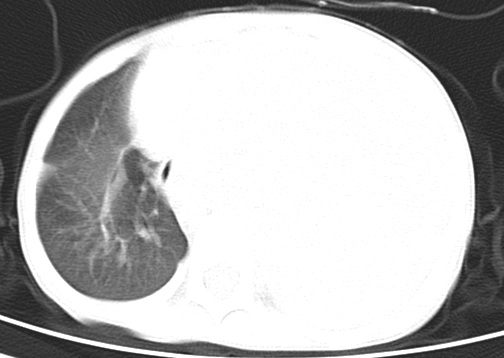

患儿 女 4岁,发热 咳嗽 胸透 考虑:左侧脓胸

左侧胸廓内见大量密实阴影,肺尖部尚有少量肺组织影,纵膈明显受压移位,肋骨未见明显受侵征象,虽然病人年龄较小,但如此大量的“积液”,还是要警惕,不同意一般感染,可结合穿刺脱落细胞学检查。

1)考虑左肺炎症感染。2)左侧大量胸腔积液。

1)考虑左肺炎症感染。2)未经穿刺只能定左侧大量胸腔积液。

左侧张力性大量胸腔积液压迫性肺不张、感染;建议治疗后复查。